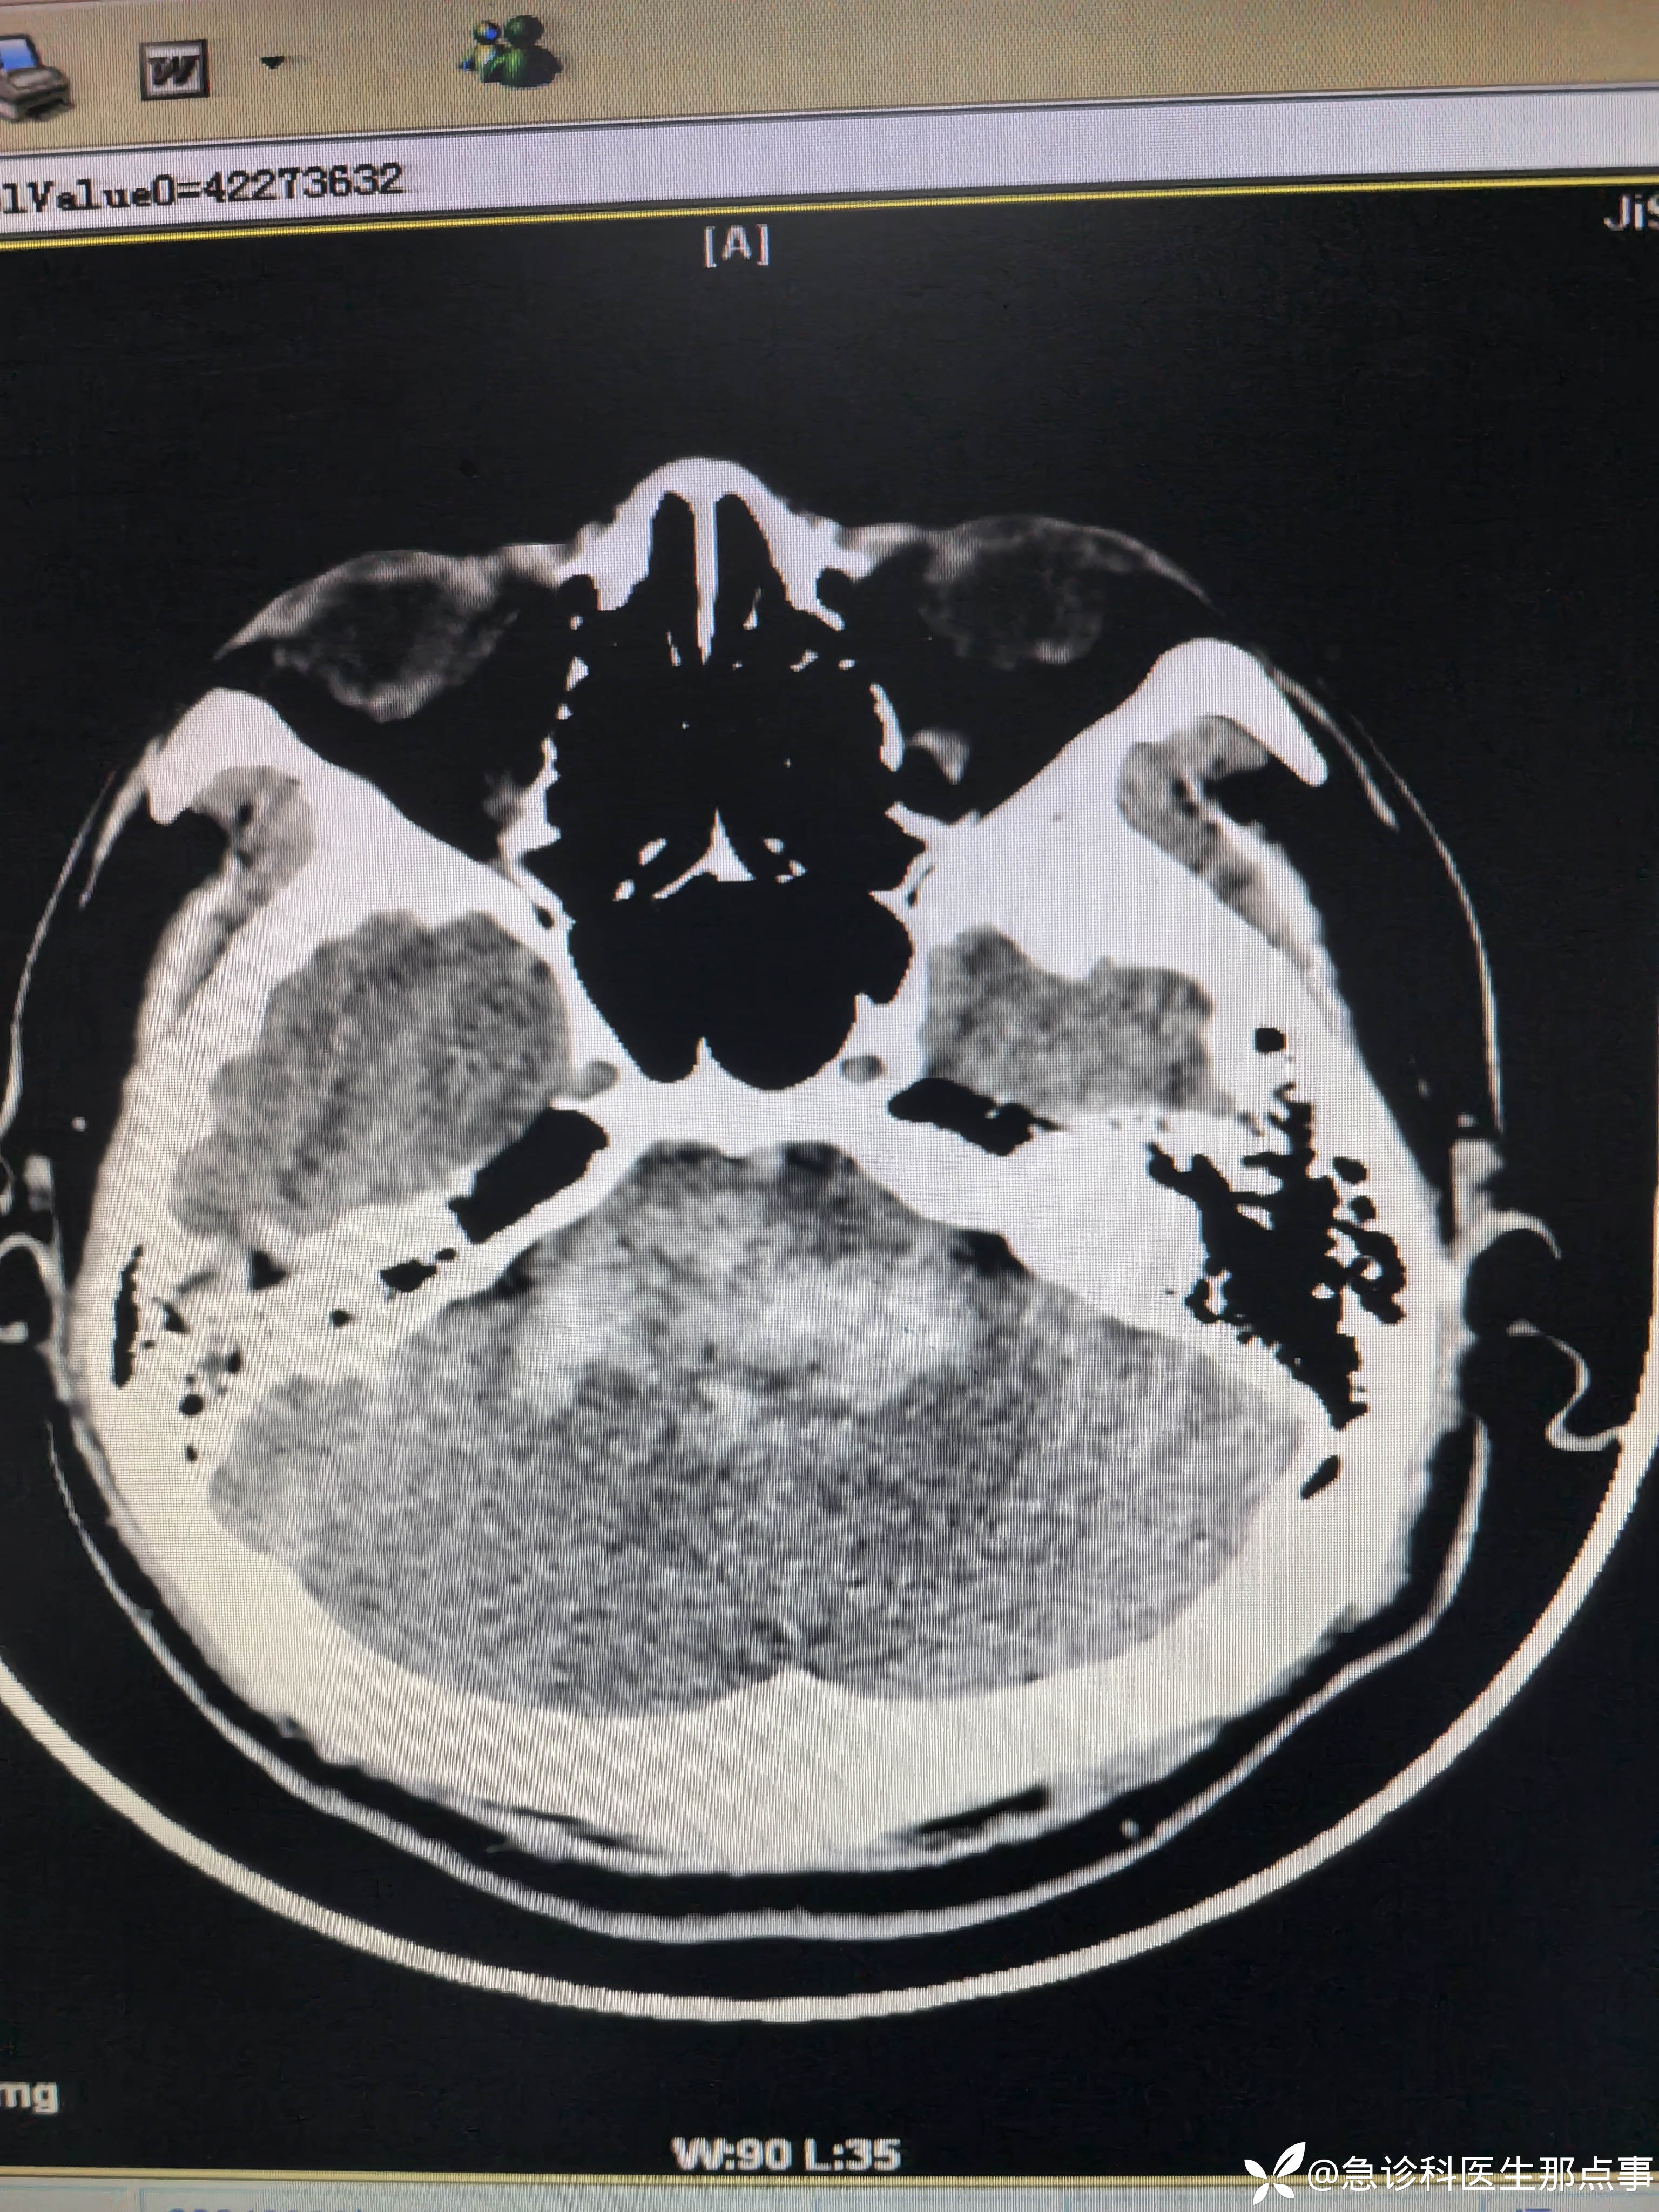

【患者信息】:男,40岁

【主诉】:突发意识不清伴双下肢间歇性痉挛抽搐半小时。

【现病史及既往史】:高血压病,间断口服药物。

【检查】:血压235/114心率82指脉氧99%意识不清,口吐白沫,双下肢间歇性痉挛抽搐。

【临床诊断】:脑干出血

【治疗经过及结果】:监护,吸氧,甘露醇快速静滴。